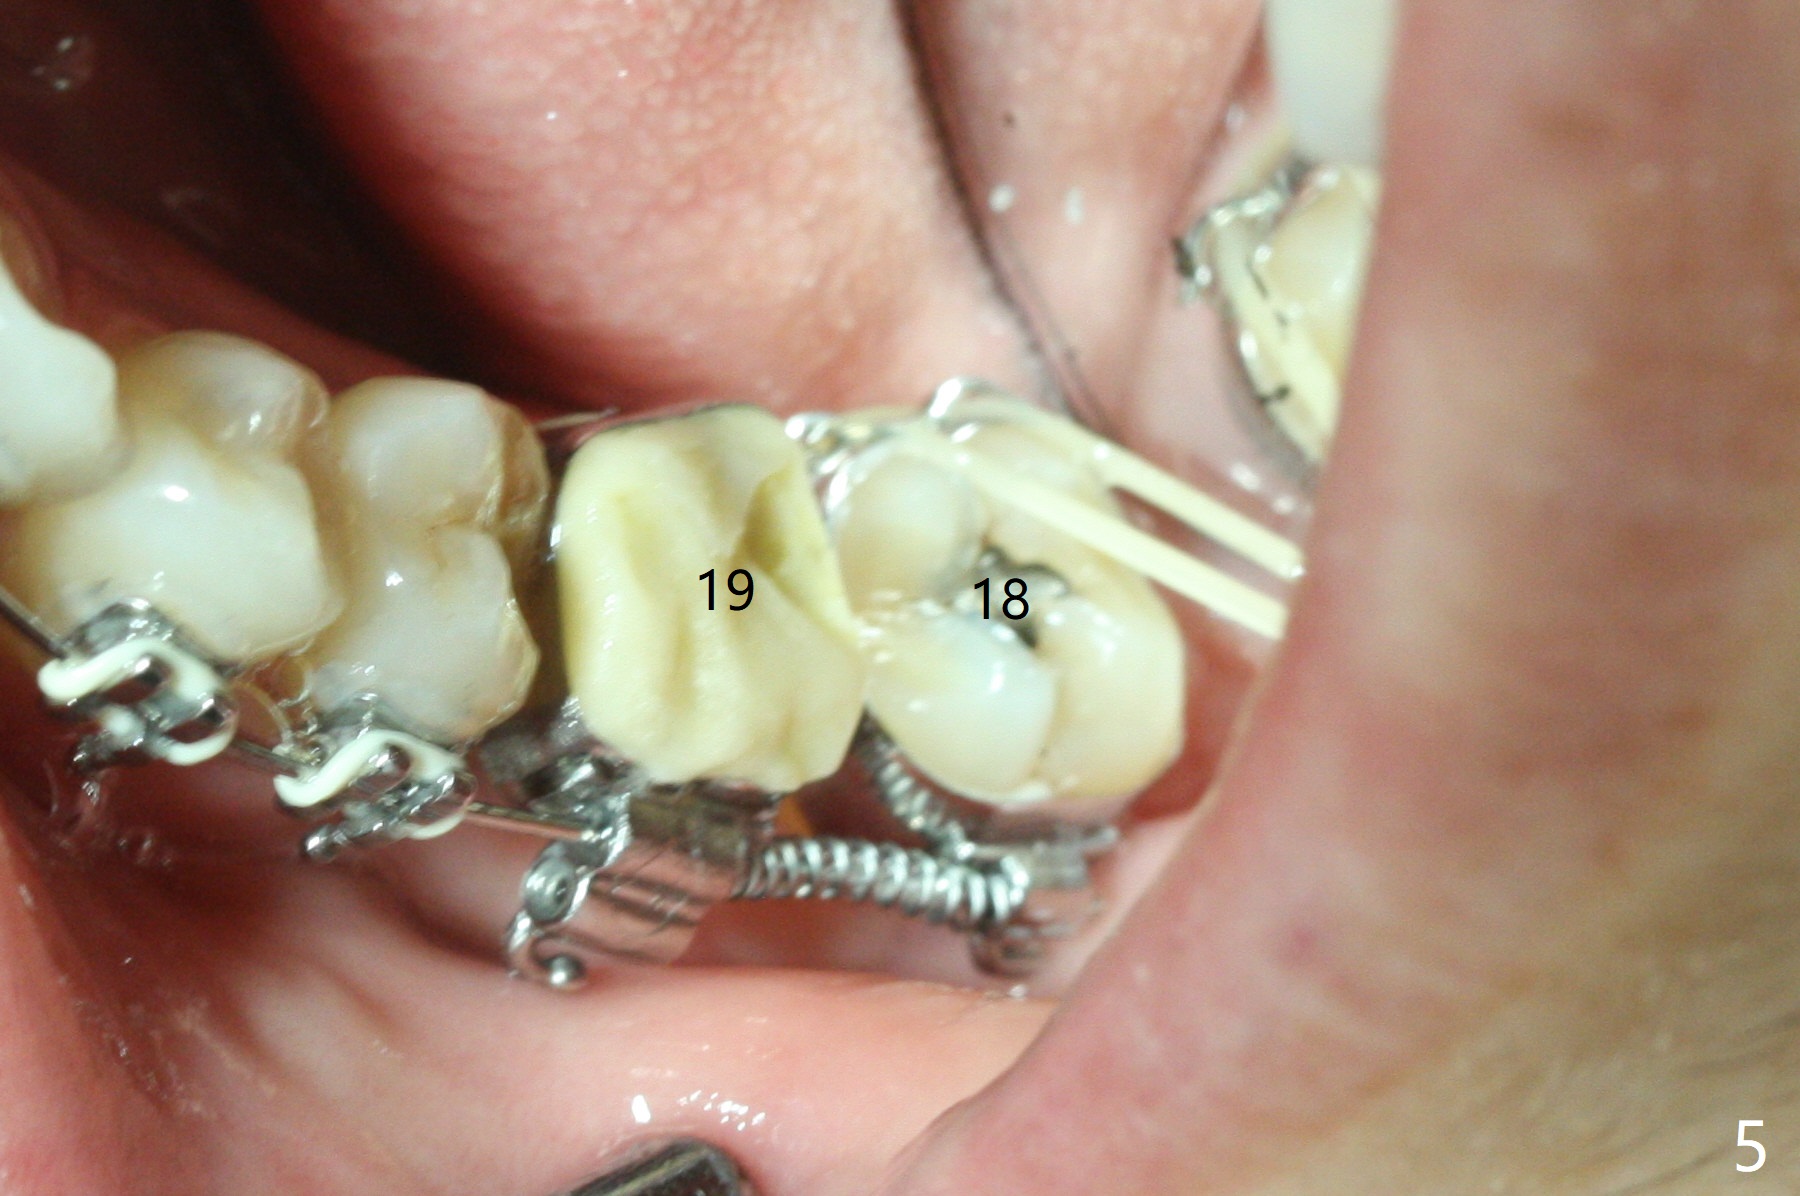

A 5x10 mm implant is intentionally placed distal at #19 using guided surgery (Fig.1). When it is osteointegrated, it will be used as an anchorage to upright the tooth #18 orthodontically. In fact the implant is mistakenly placed 1.5 mm deeper than planned without significant side effect (red dashed line: the superior border of the Inferior Alveolar Canal). The tooth #17 will be extracted before banding. The healing abutment dislodges (probably as related to deep placement of the implant) 20 days postop and is retightened. There is mild crestal bone loss 4 months postop (Fig.2). The tooth #17 is extracted with insertion of Osteogen Plug to prevent dry socket. A 5x4(2) mm cementation abutment will be placed with fabrication of a provisional with equi- or slightly subocclusal. Bands and brackets will be placed at #18-22. When open coil spring is placed between #18 and 19 with 18 ss wire, acrylic will be added to the occlusal surface of the provisional so that the tooth #18 is distalized without interference. The tooth #18 is distalized more than 1 month post placement of open coil spring (Fig.3). The tooth #18 is also lingually tilted (Fig.5), as compared to the contralateral side (Fig.4). After placement of 20 ss wire and longer coil spring, an elastic is placed between the lingual cleat of #18 and the buccal (lingual) button of #15 (Fig.5) to correct the lingual tilt. The tooth #18 is distalized ~ 1 mm shown by X-ray, although more clinically, 2.5 months post open coil spring (Fig.6). The bone density around the implant, particularly mesial, increases, as compared to Fig.2. The treatment finishes with normal overjet in the 2nd molars 11 months postop and 5 months post banding (Fig.7). It appears that the buccal groove of the lower 2nd molar (Fig.8 >) has been distalized to occlude with the mesiobuccal cusp of the upper 2nd molar (^). The width of the dense bone around the implant increases 14 months postop (3 months post cementation, Fig.9).